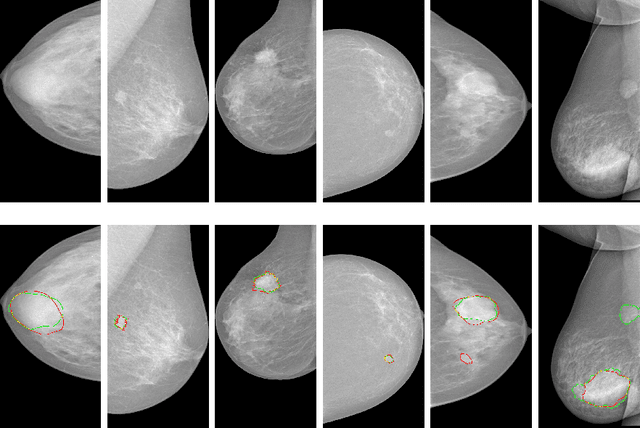

Abstract:Automatic mammogram classification and mass segmentation play a critical role in a computer-aided mammogram screening system. In this work, we present a unified mammogram analysis framework for both whole-mammogram classification and segmentation. Our model is designed based on a deep U-Net with residual connections, and equipped with the novel hybrid deep supervision (HDS) scheme for end-to-end multi-task learning. As an extension of deep supervision (DS), HDS not only can force the model to learn more discriminative features like DS, but also seamlessly integrates segmentation and classification tasks into one model, thus the model can benefit from both pixel-wise and image-wise supervisions. We extensively validate the proposed method on the widely-used INbreast dataset. Ablation study corroborates that pixel-wise and image-wise supervisions are mutually beneficial, evidencing the efficacy of HDS. The results of 5-fold cross validation indicate that our unified model matches state-of-the-art performance on both mammogram segmentation and classification tasks, which achieves an average segmentation Dice similarity coefficient (DSC) of 0.85 and a classification accuracy of 0.89. The code is available at https://github.com/angrypudding/hybrid-ds.